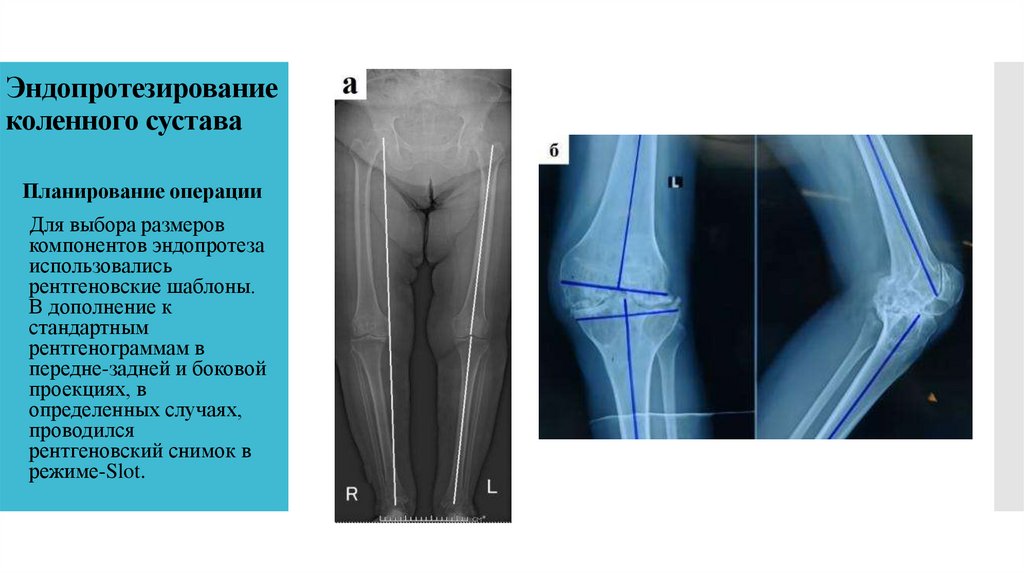

27. Эндопротезирование коленного сустава

Планирование операции

Для выбора размеров

компонентов эндопротеза

использовались

рентгеновские шаблоны.

В дополнение к

стандартным

рентгенограммам в

передне-задней и боковой

проекциях, в

определенных случаях,

проводился

рентгеновский снимок в

режиме-Slot.

28. Эндопротезы системы Vanguard фирмы Biomet (США) для коленного сустава.